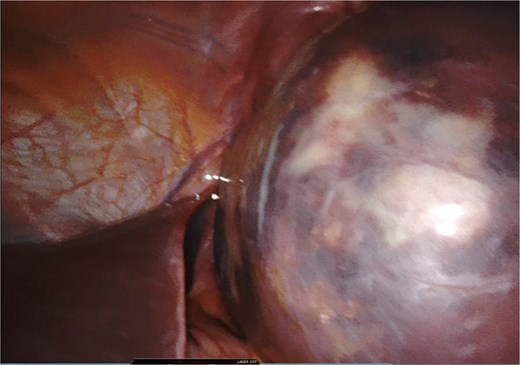

A giant splenic cyst was observed, compressing gastrointestinal organs, with limited mobilization (Fig. 3). Dissection of the splenoepiploic ligaments was performed using a bipolar energy device (Vessel Sealer), followed by dissection of the splenic flexure of the colon. The pre-splenic ligament was divided, and vascular control of the short gastric vessels was achieved. The vascular bed was identified with indocyanine green (ICG)-enhanced fluorescence (Fig. 4), and vascular control of the artery and vein was performed with a 40 mm stapler (Fig. 5). The splenophrenic ligament was divided, and the splenic bed was skeletonized (Fig. 6).

Intraoperative visualization of enlarged spleen and intraparenchymal cyst.